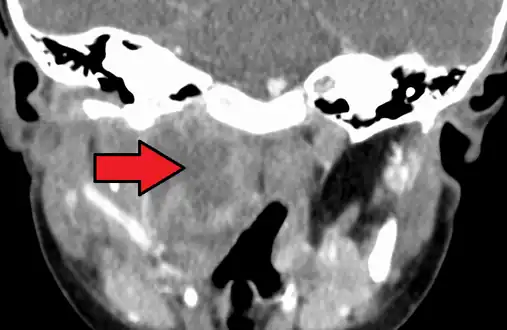

Large retropharyngeal abscess as seen on CT

A computed tomography (CT) scan is the definitive diagnostic imaging test.[4]